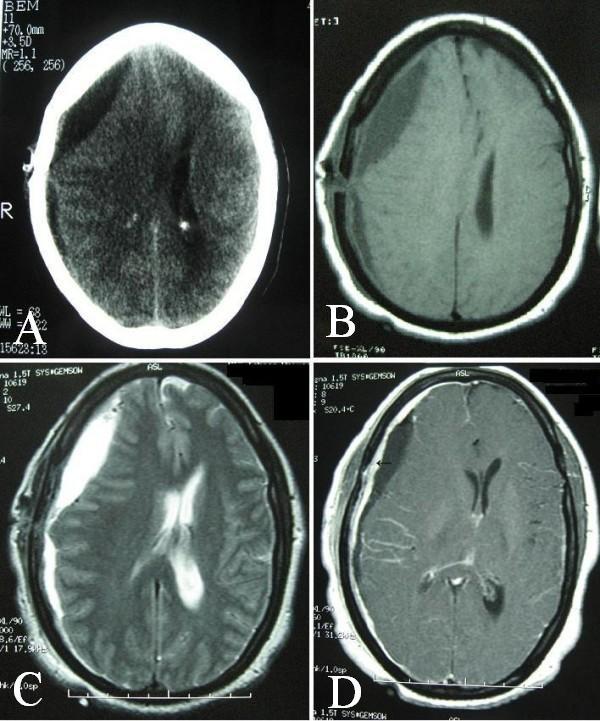

A 44-year old woman with gastric adenocarcinoma was presented with headache and a hypodense subdural collection in right fronto-parietal in brain CT. Burr-hole irrigation was performed with the impression of chronic subdural hematoma, but nonhemorrhagic xantochromic fluid was evacuated without malignant cell. Brain CT on the 11th day depicted fluid re-accumulation and noticeable midline shift, necessitating craniotomy and removing the affected dura.

一名44岁胃腺癌女性患者,因头痛就诊,脑部CT显示右侧额顶叶有一低密度硬膜下积液。最初按慢性硬膜下血肿行钻孔冲洗引流术,但引出的是非血性黄色液体,未发现恶性细胞。术后第11天脑部CT显示积液再次积聚且中线明显移位,需行开颅手术并切除受累硬脑膜。